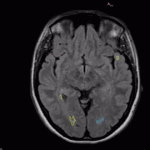

Le premier, Pixyl.Neuro.MS, est dédié au diagnostic et au suivi des patients atteints de maladies affectant la substance blanche du cerveau, comme la Sclérose en Plaques. Il permet la détection des lésions spécifiques sur les images IRM, ainsi que leur quantification et leur classification selon leur localisation dans les régions spécifiques du cerveau. En cas d’IRM antérieure, la solution est également à même d’évaluer l’évolution dans le temps de chaque lésion, permettant un suivi fin de l’activité de la maladie.

Le second volet, Pixyl.Neuro.BV, est un outil de volumétrie cérébrale. Il identifie les différentes structures du cerveau, calcule leur volume ainsi que l’évolution des volumes dans le temps, et compare les valeurs du patient aux valeurs d’une population normale “saine”. Cet outil permet notamment l’aide au diagnostic et au suivi de la maladie d’Alzheimer, mais est également précieux pour d’autres types de démences.